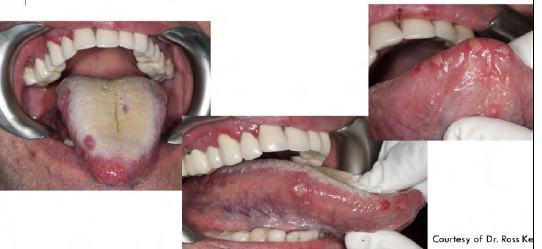

These photos represent

gingivostomatitis

multiple irregularly shaped

ulcers present on the fixed and movable mucosa, bilaterally

What is this infectious disease?

What probably this patient also have?

HSV1: primary herpetic gingivostomatitis

there are multiple irregularly shaped

ulcers present on the fixed and movable mucosa –> most likely

diagnosis is primary herpetic gingivostomatitis since the patient has

fever and malaise.